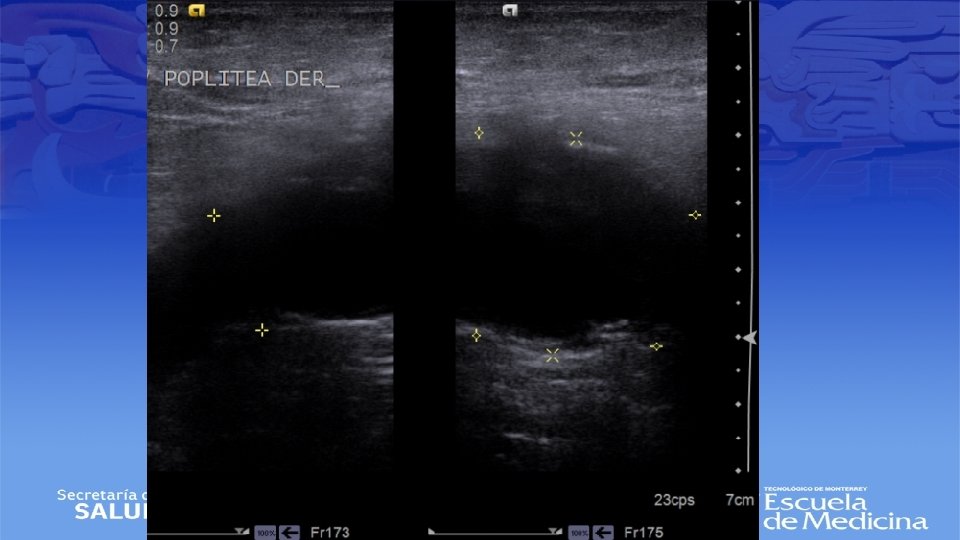

ECO Doppler

Impresión Diagnóstica • IDX: Aneurisma Poplíteo bilateral

Diagnostico • Ultrasonido Doppler, Angiotac, angioresonancia • Arteriografía es mas apropiada para sintomatología aguda